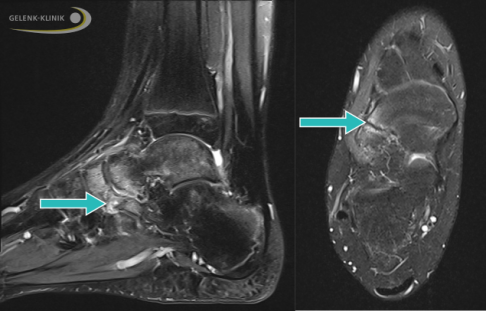

Magnetresonanztomographie (MRT) bei einem Patienten mit kompletter Koalition zwischen Sprungbein und Fersenbein (Kreis). Blick von hinten auf die Ferse: Rechts besteht eine nicht normale Verbindung der beiden Knochen. Man spricht von einer talokalkanearen Koalition. © Gelenk-Klinik

Magnetresonanztomographie (MRT) einer partiellen Koalition zwischen Sprungbein und Fersenbein (Pfeil) mit deutlichem Knochenödem als Zeichen einer akuten Entzündung. © Gelenk-Klinik